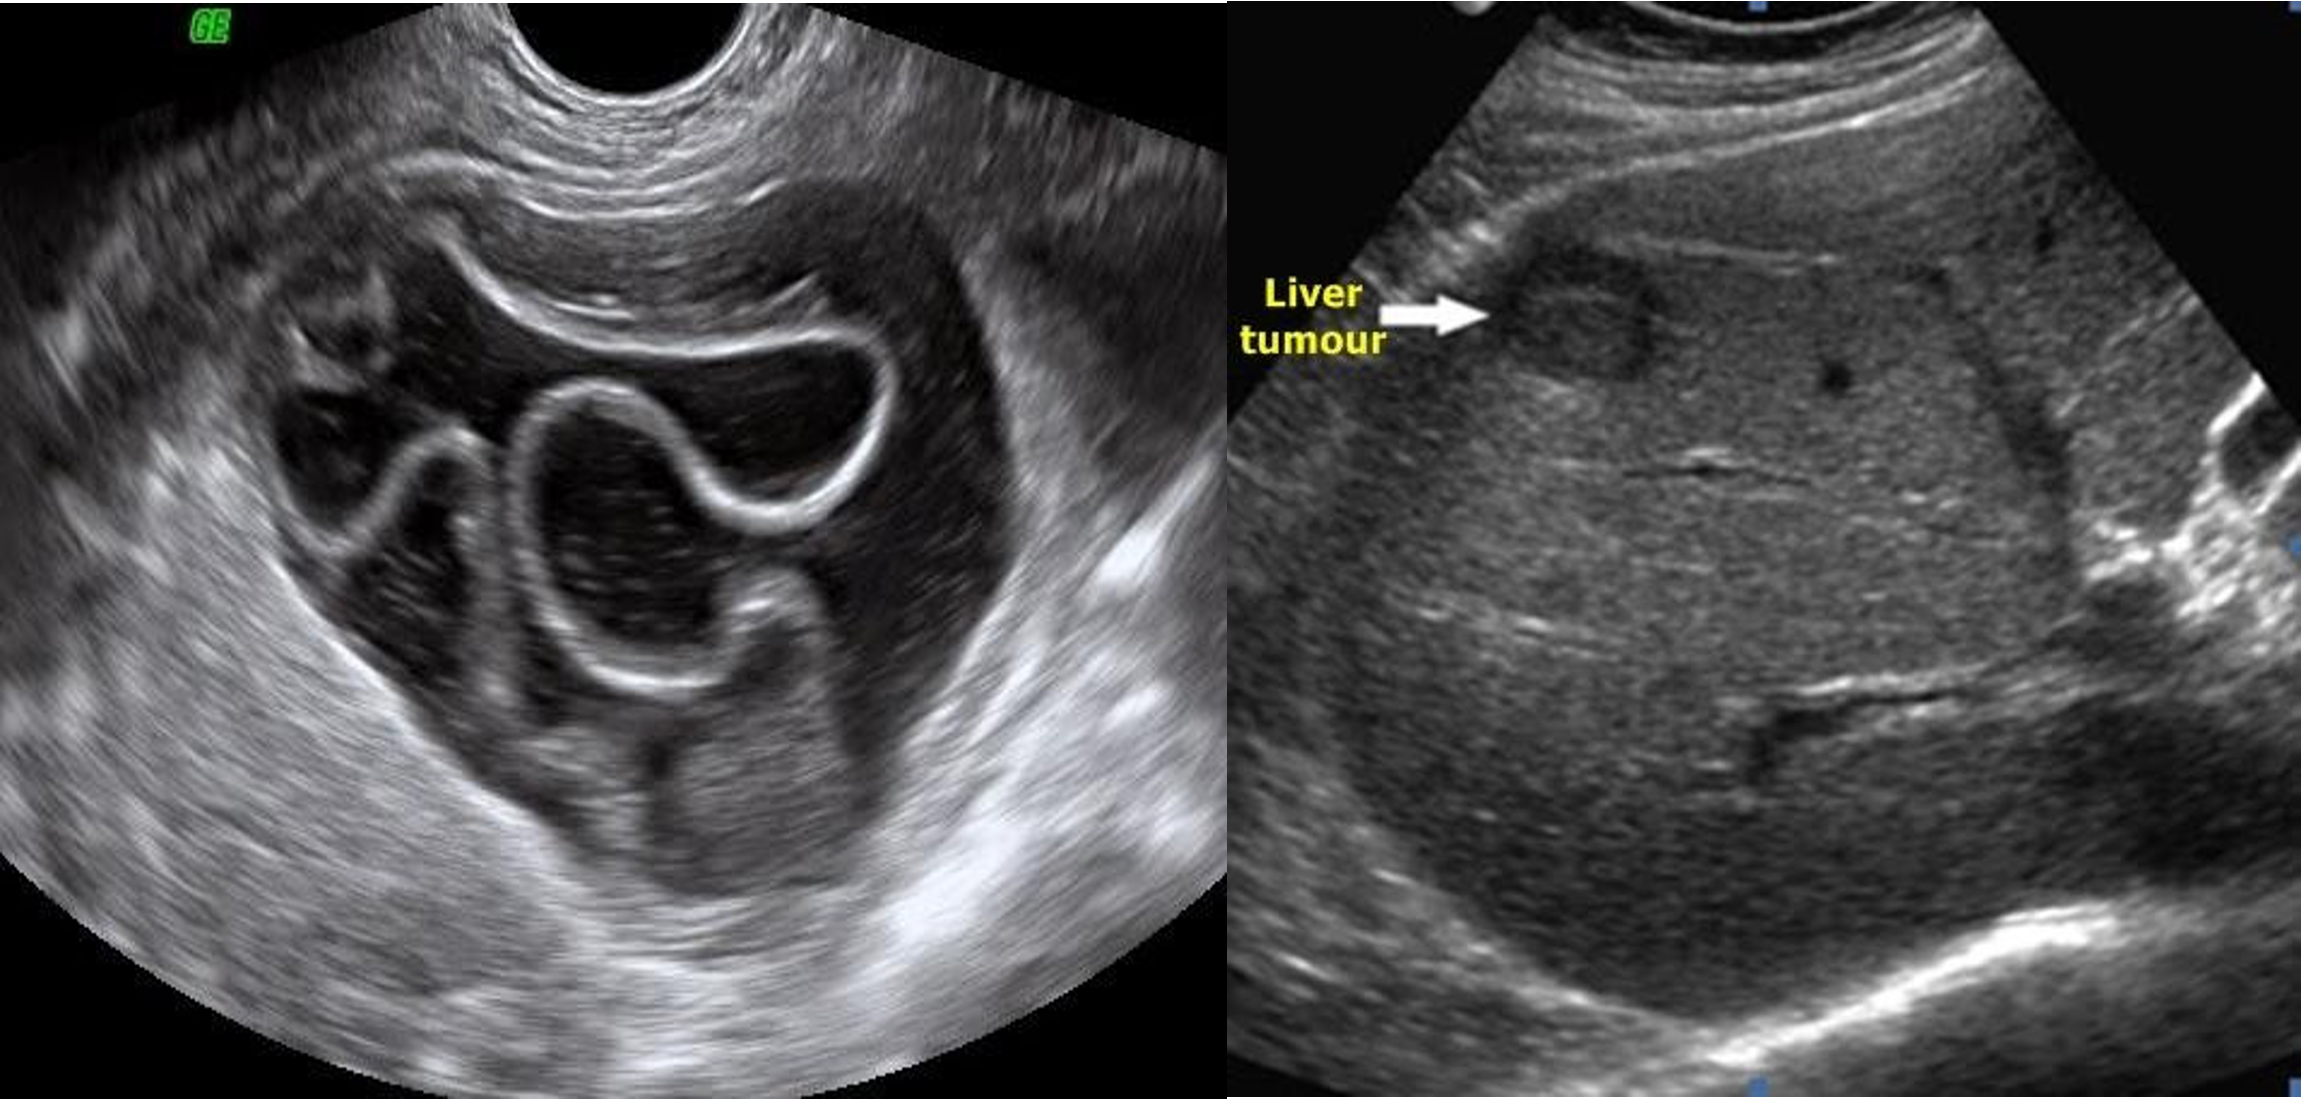

U/S

- chronic chole

- hyperechoic - post acoustic shadow…

- acute cholecystitis

- acute edematous thick gallbladder

- stone tumour

hydiatted

HCC